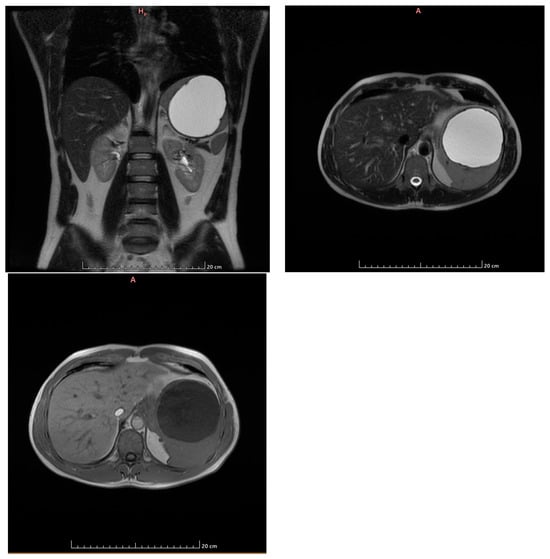

- Capillary hemangioma hepatic segment VII of 8 mm diameter.

- Grade I splenomegaly with simple voluminous splenic cyst, 10 cm in diameter.

- Accessory spleen adjacent to the lower pole of the spleen.